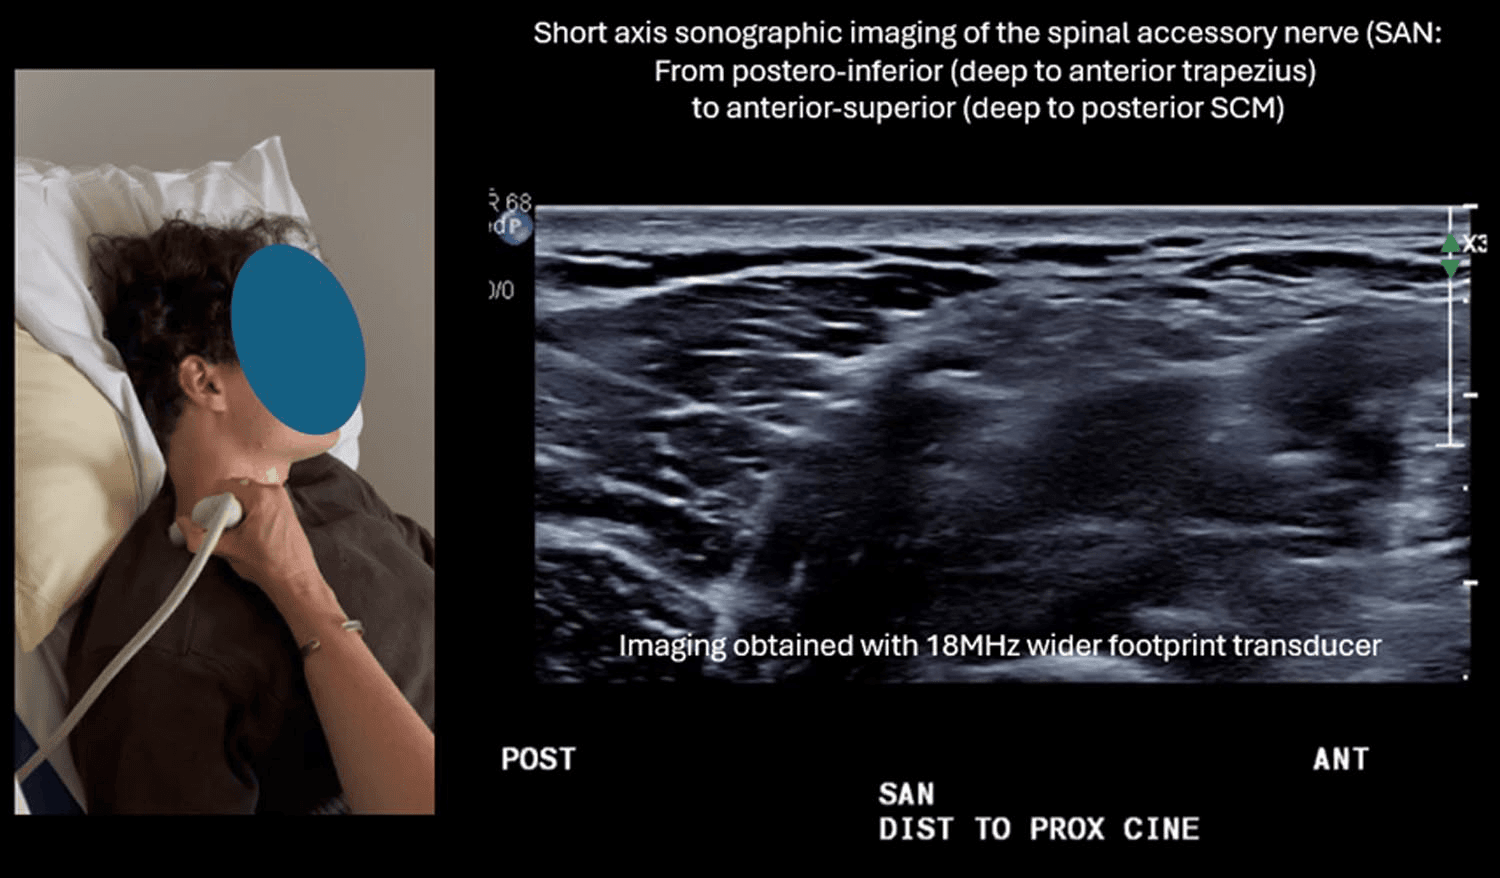

흉쇄유돌근 - 그림 4. 흉쇄유돌근(sternocleidomastoid, SCM) 심부를 주행하는 척수부 Figure 4. 그림 4. 흉쇄유돌근(sternocleidomastoid, SCM) 심부를 주행하는 척수부신경(SAN)입니다. (a) 단축 정적 영상입니다.

흉쇄유돌근 심부를 주행하는 척수부신경의 초음파 영상에서는 근육 섬유 사이로 지나가는 신경의 모습을 단축면에서 명확히 관찰할 수 있습니다.